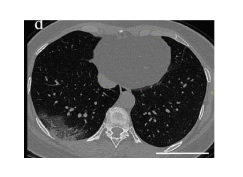

CT Data set

✓ 코로나 양성 이미지 349장

✓ 코로나 음성 이미지 397장

✓ carry more information compared to chest X-rays

X-ray의 Epistemic Uncertainty 는 상대적으로 낮고, CT 이미지는 꽤 높은것을 확인할 수 있습니다.

앞서 말씀드렸듯 CT 이미지는 원래 흉부를 관통하여 찍는 3D 이미지인데요, 이를 모두 사용하지않고 임의로 한 장을 선택해 분류를 진행하였으니 x-ray에 비해 불확실성이 높게 나타난 것이 아닌가 싶습니다. (가령 Covid를 분류하기 위한 설명력 높은 feature를 추출할 수 있는 위치에서 찍은 이미지가 아니었다던가..)